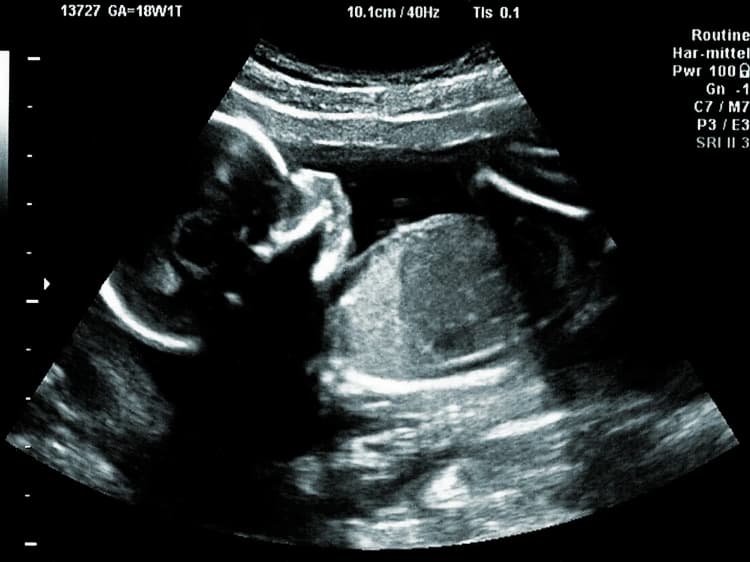

Understanding pregnancy weeks and trimesters can help you track the progress of your pregnancy and anticipate key milestones and developments for you and your baby. Each week and trimester represents distinct stages of growth and milestones in your pregnancy journey.

Pregnancy by Weeks

Each stage of pregnancy is a profound and transformative experience. From the very beginning to the moment you welcome your newborn, each week brings its own special changes as both your baby and your body grow and evolve.